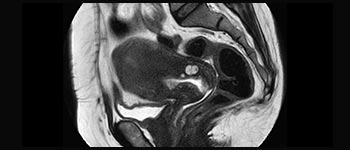

Find the right clinical applications for your needs